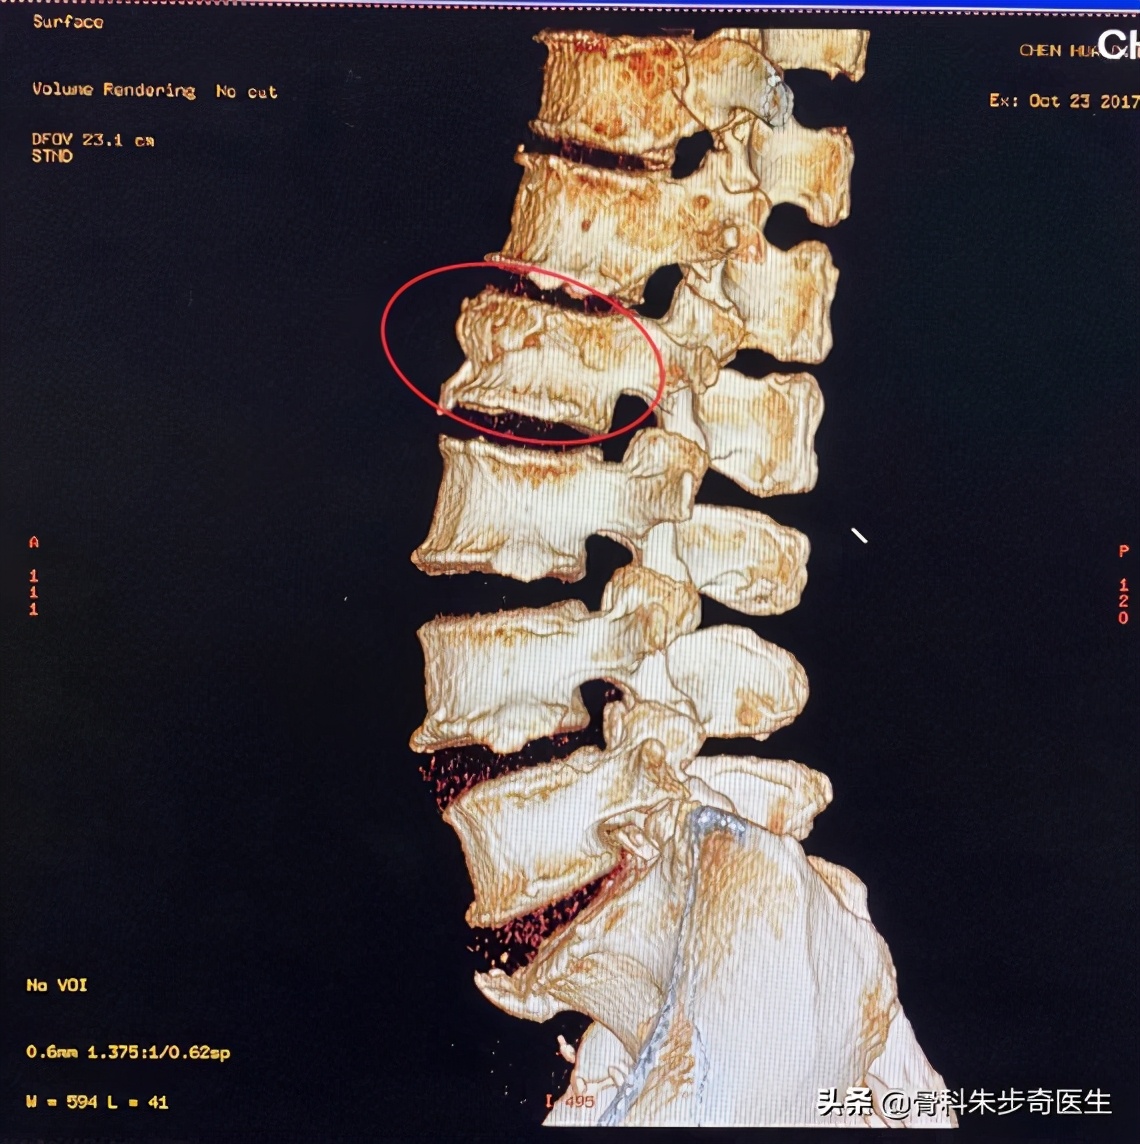

从片子上可以看出来,她的腰2椎体骨折,所以就安排她住院了,40床。

这是腰2椎体,而画圈的部位就是腰椎后方的结构,这个结构是非常重要的结构,这里是否存在骨折是判断是否手术的比较关键的一点。

根据这3点,患者神经功能是完好的,椎体的高度也基本压缩不多,后方也并没有出现骨折。